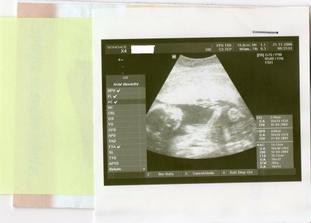

21.11. KO+velký ultrazvuk...........20+1 na velkém UTZ mimi v pořádku,jen se nám nechtělo ukázat.A dr.mě pro jistotu posílá ne genetický UTZ,objednala jsem se do Libereckého Genettu.Tam jedeme 28.11.

Tak jsme po UTZ,miminko se mlelo a krásně hýbalo,vše bylo vidět,vše je v pořádku a hlavně

JE TO KLUK....TAKŽE BUDEME MÍT MATYÁŠKA🙂))))))